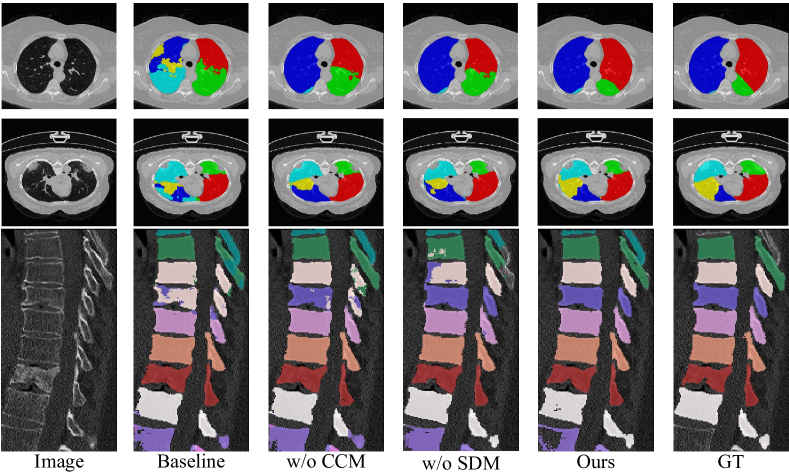

Firstly, we investigate the effectiveness of two proposed components (SDM and CCM) on lobe and vertebrae data. Employing the proposed SDM makes our PnPNet more powerful for modeling complicated boundary regions. And SDM attempts to enhance boundary feature representations by introducing pushing forces based on diffusion theory. For VerSe 2019, incorporating SDM into the baseline model will boost the segmentation performance on the cervical, thoracic, and lumbar vertebrae, with and Dice increases on cervical and thoracic vertebrae. For the clean lung lobe, we calculate the confusion matrix to measure the segmentation performance, especially for right lobes. As depicted in Figure 10, some voxels in the right middle lobe are wrongly classified as categories of right upper and lower lobes, and parts of the right upper lobe are prone to misclassification as the right middle lobe. And introducing SDM can substantially improve the problem above. For the fused lung lobe, we provide T-SNE visualizations of the decoded feature in Figure 8. We can figure out that class-wise features are better divided into five different semantic classes after the baseline model is integrated with SDM. And this phenomenon indicates that SDM can enlarge the inter-class distance, then discriminate the inter-class boundaries between different anatomies.

Then we make a thorough inquiry on the efficacy of CCM. Incorporating the pulling branch into the baseline model leads to considerable performance improvements for lung lobe datasets. Specifically, for the fused lung lobe, the structure of CCM brings and Dice increases on the left and right lobes. While for the vertebrae data, CCM serves as a pulling force to stretch the intersected boundary region, then squeezes each vertebra to improve the segmentation consistency. As illustrated by Figure 8, the class-wise features can be better divided into different classes. On the one hand, the intra-class distance is largely reduced, which means that CCM can tighten data distributions of each semantic class. On the other hand, inter-class distance has been expanded, which indicates that inter-class boundaries between anatomies can be more precisely segmented.

By combining these two modules, the segmentation performance on boundary predictions is further boosted due to adversarial forces. As illustrated in Figure 7, pulling tokens tend to enlarge the inter-class boundary region to amplify the boundary uncertainty, while pushing tokens try to squeeze it. Thus, boundaries between different anatomies are more precisely segmented after reaching the dynamic equilibrium state. Here we pay more attention to the evaluation metric on boundary surfaces. The ASSD value has decreased from 1.674mm to 1.171mm for the clean lung lobe, from 6.210mm to 1.317mm for the fused lung lobe, and from 3.73mm to 3.04mm for the vertebrae. This improvement reveals that adversarial pulling and pushing forces help to more precisely localize uncertain boundaries. However, after introducing CCM to the baseline model with SDM, the segmentation performance for cervical vertebrae declines slightly while thoracic and lumbar vertebrae are finely segmented, which might result from the biased ratio between three kinds of vertebrae [20]. And the same situation comes to the segmentation performance of left lobes. We argue that CCM is essentially effective in clustering five lobes, while class distributions of right lobes are different from those of left lobes. And neural networks exert the boundary shape constraint of right lobes to left lobes due to the class imbalance. Furthermore, Figure 9 exhibits the ablation visualizations for key components with a vertebral CT case. Adding SDM and CCM achieves a finer and more consistent prediction, especially for boundaries.